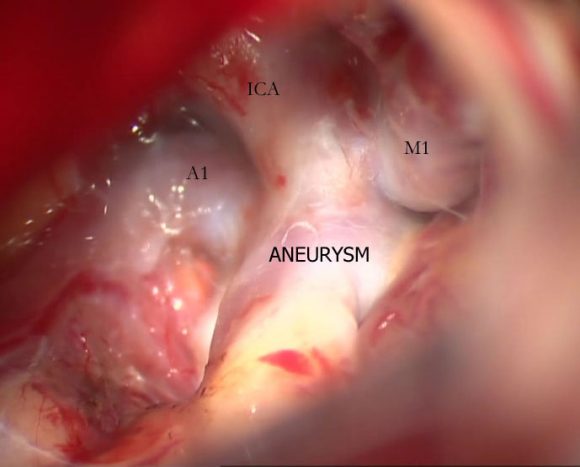

Aneurysms

Aneurysms are balloon-like outpouchings from an intracranial artery, that can rupture and present as subarachnoid hemorrhage. SAH constitutes an emergency, and if severe can be life threatening. Management is early diagnosis by brain imaging and cerebral angiography, followed by definitive treatment in the form of surgical clipping or endovascular coiling.